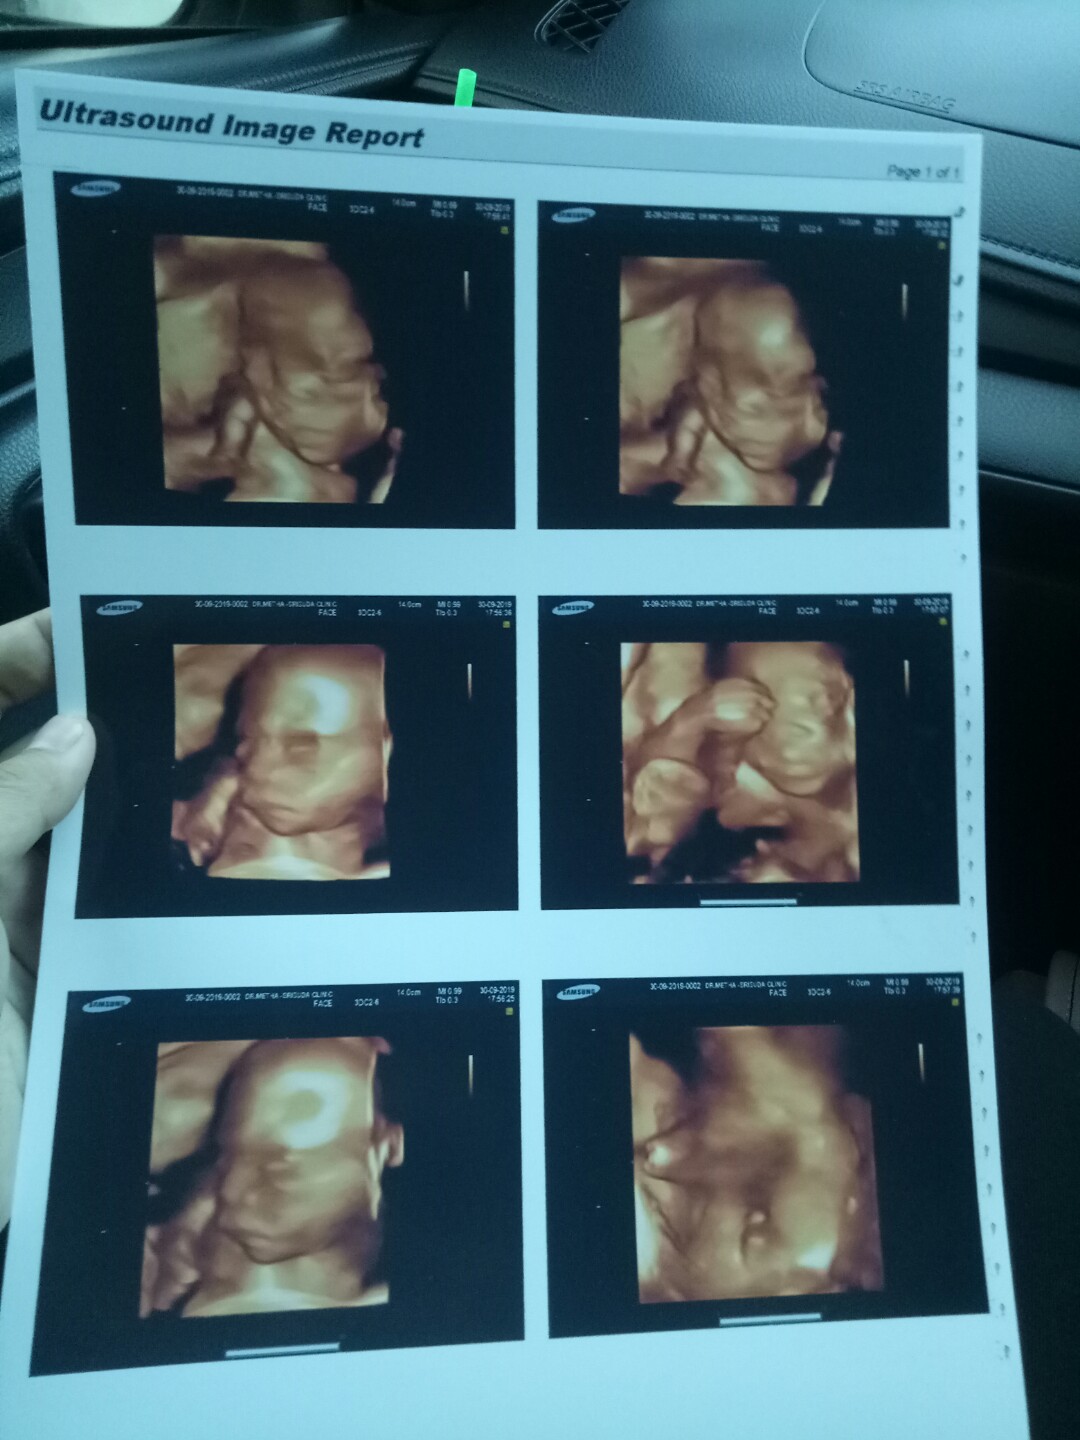

หญิงจ้า